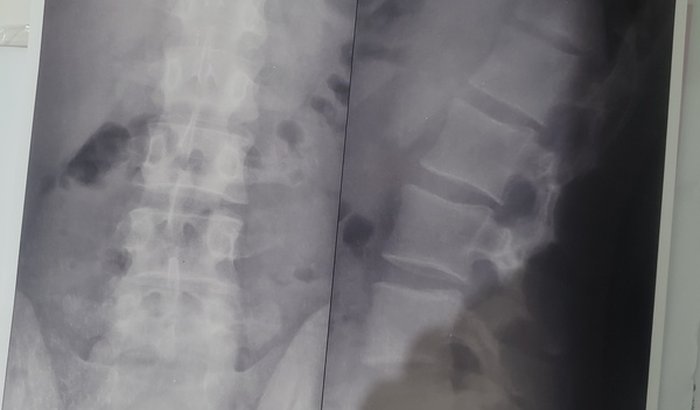

Salve guys, me chamo Eduardo tenho 23 anos e à aproximadamente 1 mes atrás fui diagnosticado com câncer e estou na batalha para poder juntar uma grana e fazer a cirurgia para remover o tumor, a cirurgia ta por volta de R$21.000,00